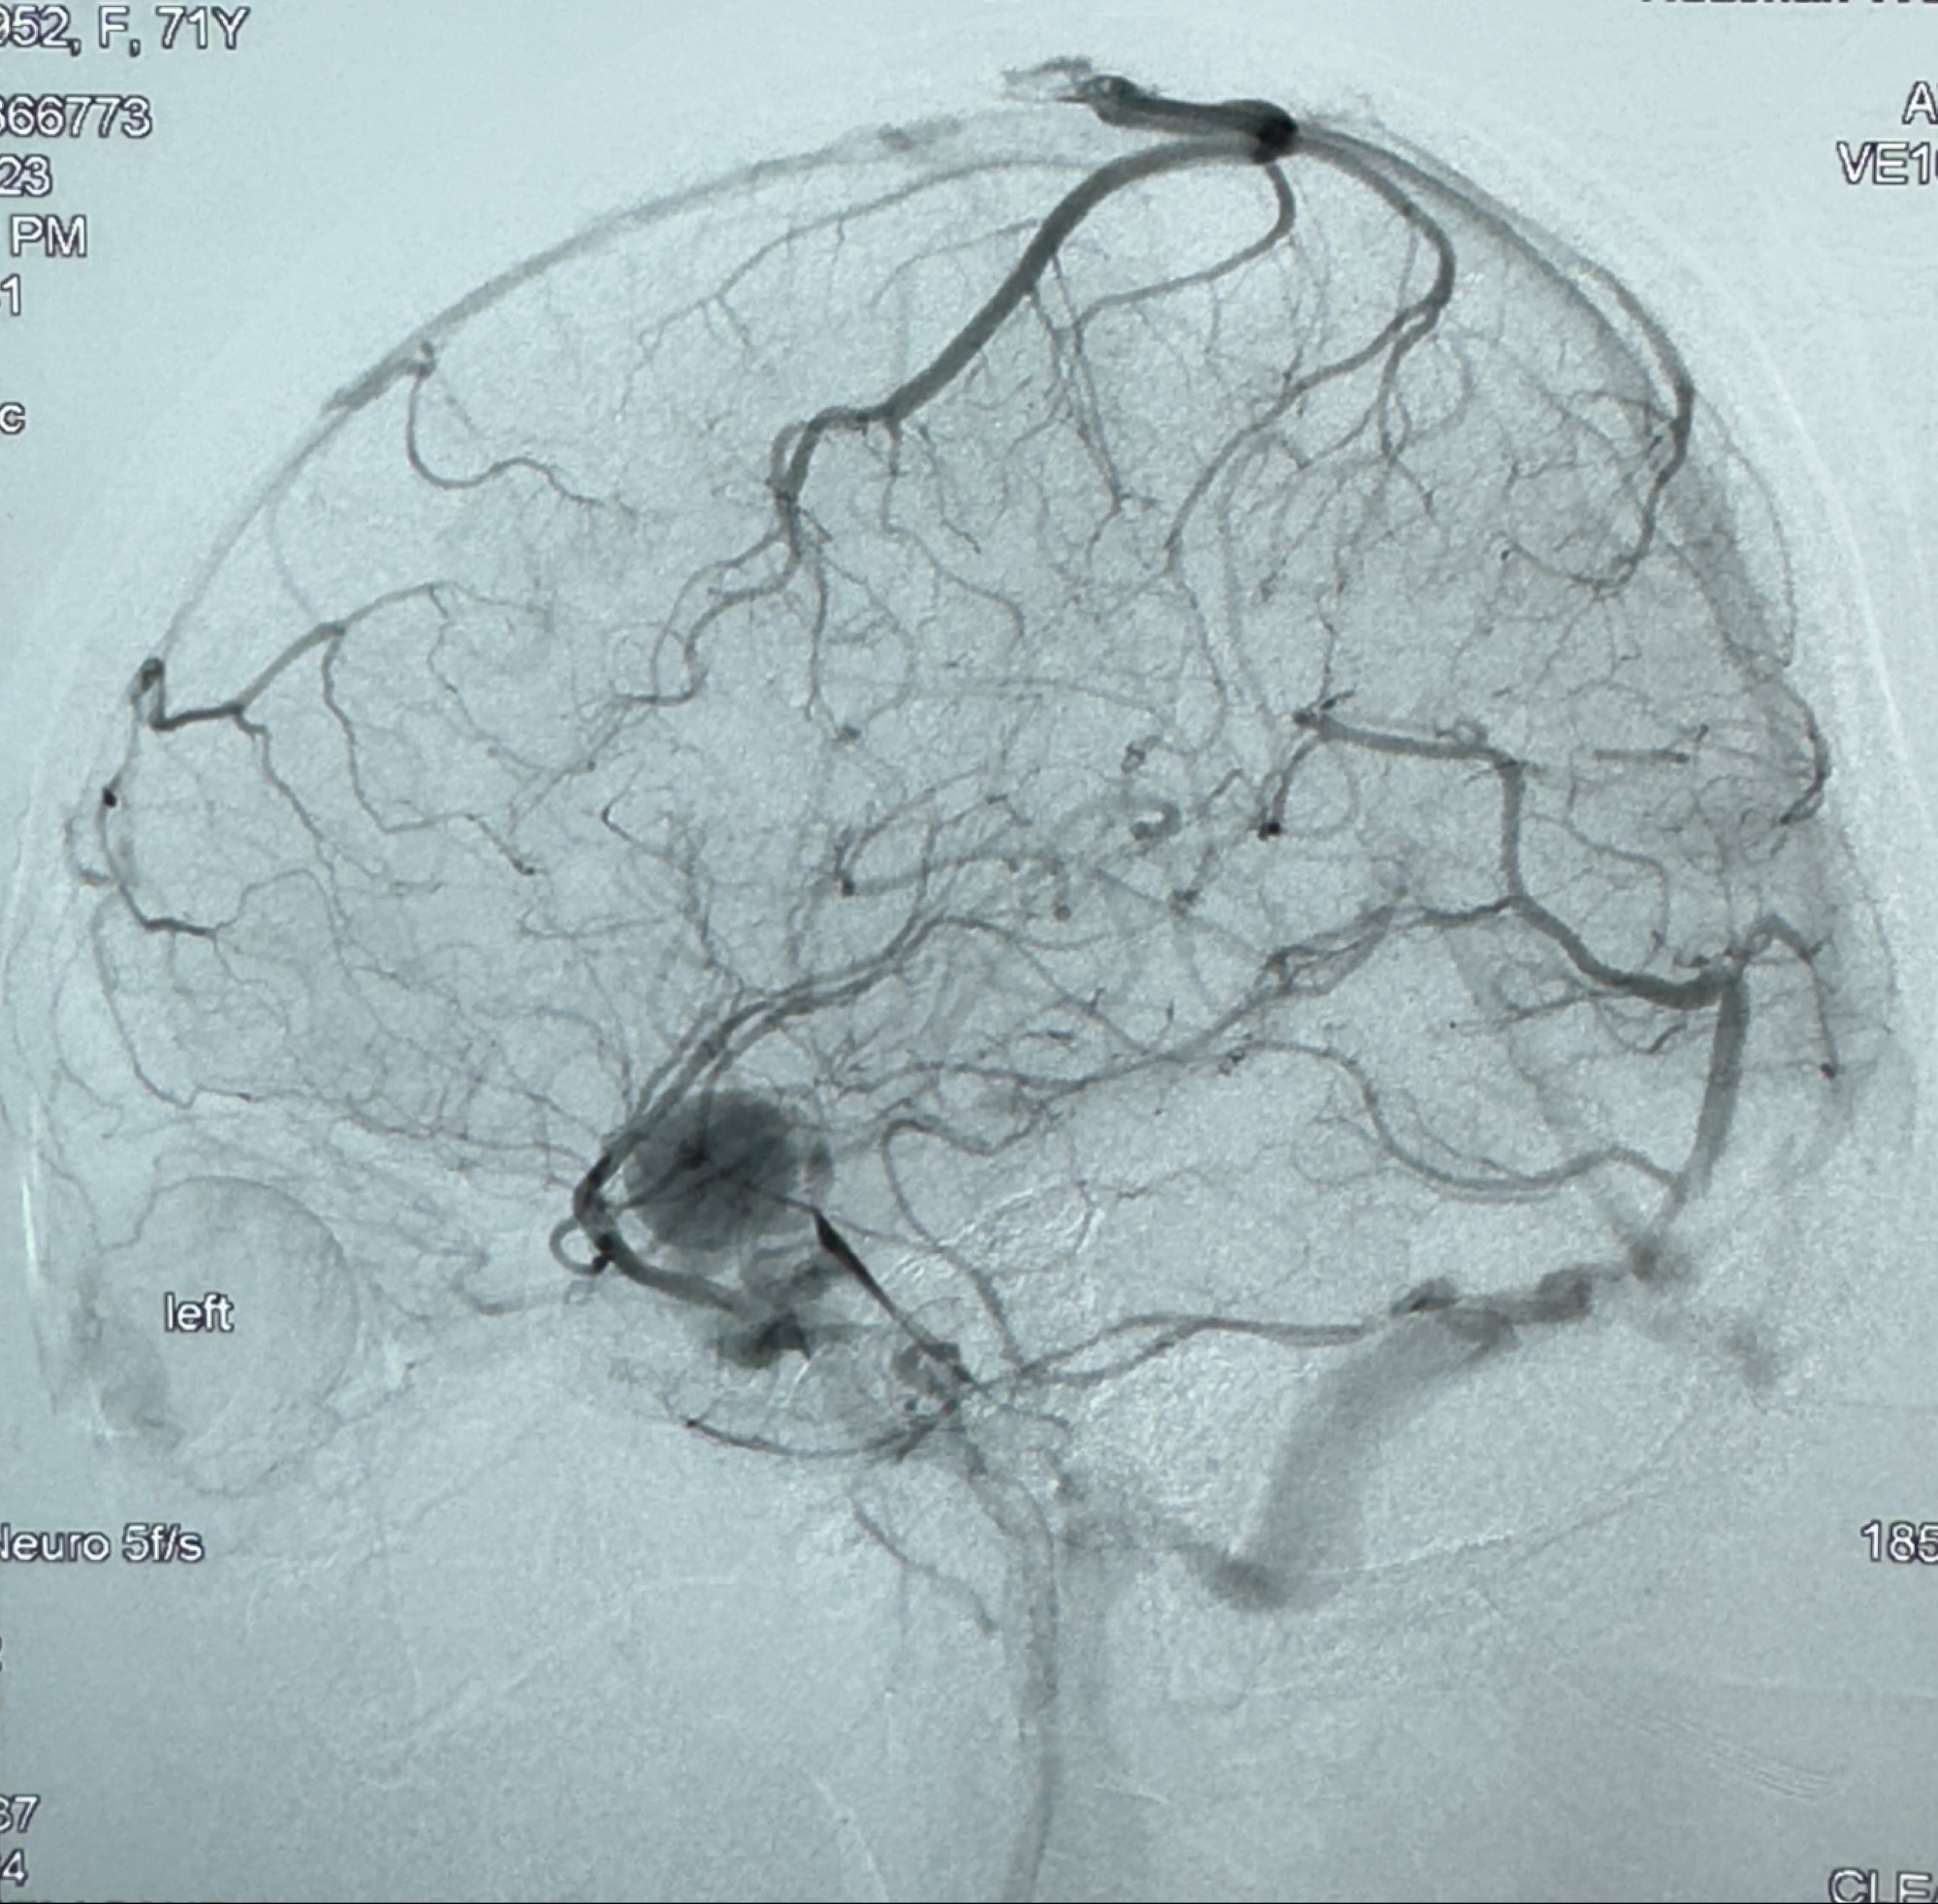

现病史:患者诉2年来反复发作性头痛,顶枕部为主,因自己考虑高血压可能,未予系统检查;患者约20日前无明显诱因下突发剧烈头晕,有天旋地转感,不能睁眼,伴视物模糊;外院查头颅MRI+MRA提示:左侧颈内动脉C6段动脉瘤;遂至复旦大学附属华山医院就诊,于2023-12-08行全脑血管造影提示:右侧颈内动脉C6段动脉瘤,瘤颈6.68mm,动脉瘤大小13.28*12.34mm,建议行密网支架辅助栓塞术治疗,因缺乏相关材料遂出院。现患者仍有顶枕部头痛不适,为求进一步诊疗脑血管病变至我科就诊,收治入院。

2023-12-08 复旦大学附属华山医院 全脑血管造影:右侧颈内动脉C6段动脉瘤,瘤颈6.68mm,动脉瘤大小13.28*12.34mm

测量动脉瘤的大小:16*13.8*7.6mm大小,较原先变大,考虑双抗后瘤内血栓溶解可能